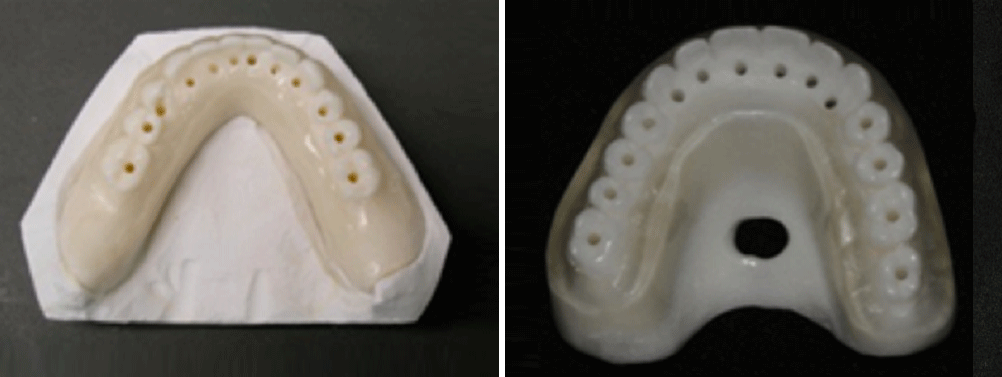

Seconda Fase

Realizzazione di protesi totale

Terza Fase

Duplicazione in materiale bariato radiopaco (Dima Radiografica)

Sesta Fase

Realizzazione della dima chirurgica

Realizzazione del manufatto protesico